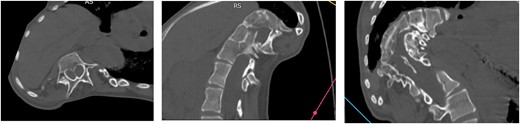

Computed tomography (CT) visualizes diastematomyelia in the form of a calcar at the level of Th11, Th12, L1 vertebrae (Fig. 4).

Magnetic resonance imaging (MRI) visualizes the separation of the spinal cord into two arms at the Th11 level (Fig. 5).